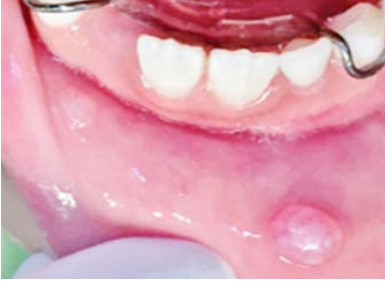

Paciente femenino de seis años de edad, sin antecedentes patológicos de relevancia, quien inicia su padecimiento actual un mes antes de solicitar atención en el departamento de Odontología Pediátrica de la Facultad de Odontología Unidad Saltillo, de la Universidad Autónoma de Coahuila, para la evaluación de una lesión labial asintomática. En la exploración extraoral no se identificaron alteraciones, mientras que de forma intraoral se observaron dos nódulos translúcidos, de base sésil, consistencia fluctuante y superficie lisa, localizados en mucosa labial inferior, el mayor midiendo 0.6 × 0.5 × 0.4 cm, y uno más pequeño, de características semejantes y adyacente al primero. Cabe destacar que la paciente portaba un mantenedor de espacio removible, funcional, inferior desde hacía un mes. Se observó que ambos nódulos coincidían con la región en que los ganchos del mantenedor contactaban con la mucosa labial (Figura 1).

Figura 1: Imagen clínica inicial. En mucosa labial inferior se observan dos nódulos bien delimitados, del mismo color de la mucosa, a nivel de los ganchos del mantenedor de espacio removible.